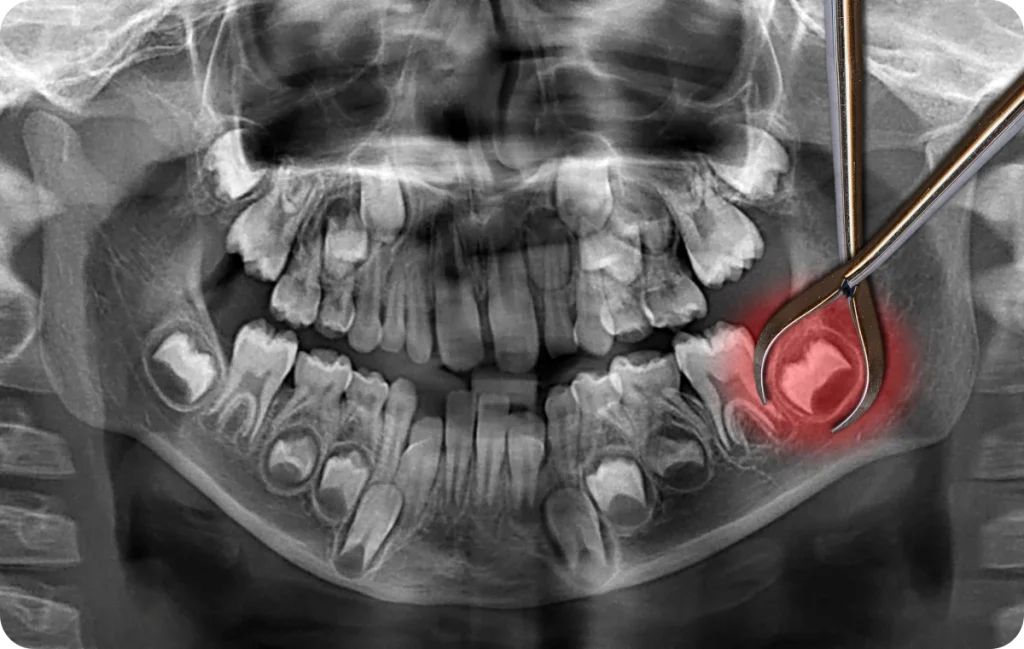

Les examens radiographiques sont essentiels pour évaluer cette situation et orienter la décision de suivi ou de prise en charge.

- Imagerie dentaire

La radiographie panoramique est couramment utilisée pour évaluer les dents de sagesse. Elle offre une vision globale des mâchoires et permet d’analyser la position des dents, leur orientation et leur proximité avec les structures voisines. Cet examen aide à établir un diagnostic précis et à déterminer la conduite à tenir.